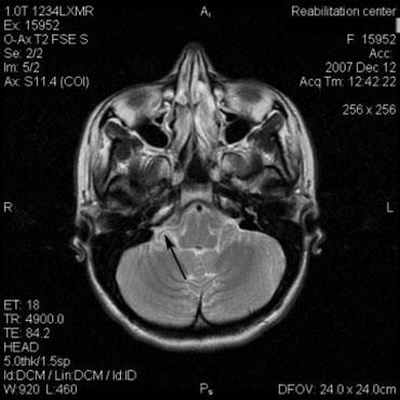

На корональной томограмме с обеих сторон хорошо видны тройничные нервы

На аксиальной и сагиттальной томограммах четко визуализируется правый тройничный нерв и прилегающая к его верхнему контуру правая верхняя мозжечковая артерия

Аксиальный срез (А, Б), сагиттальная проекция (В). Определяется нейроваскулярный конфликт между артерией и тройничным нервом. Компрессия тройничного нерва прилежащей к нему артерией обозначена стрелкой.